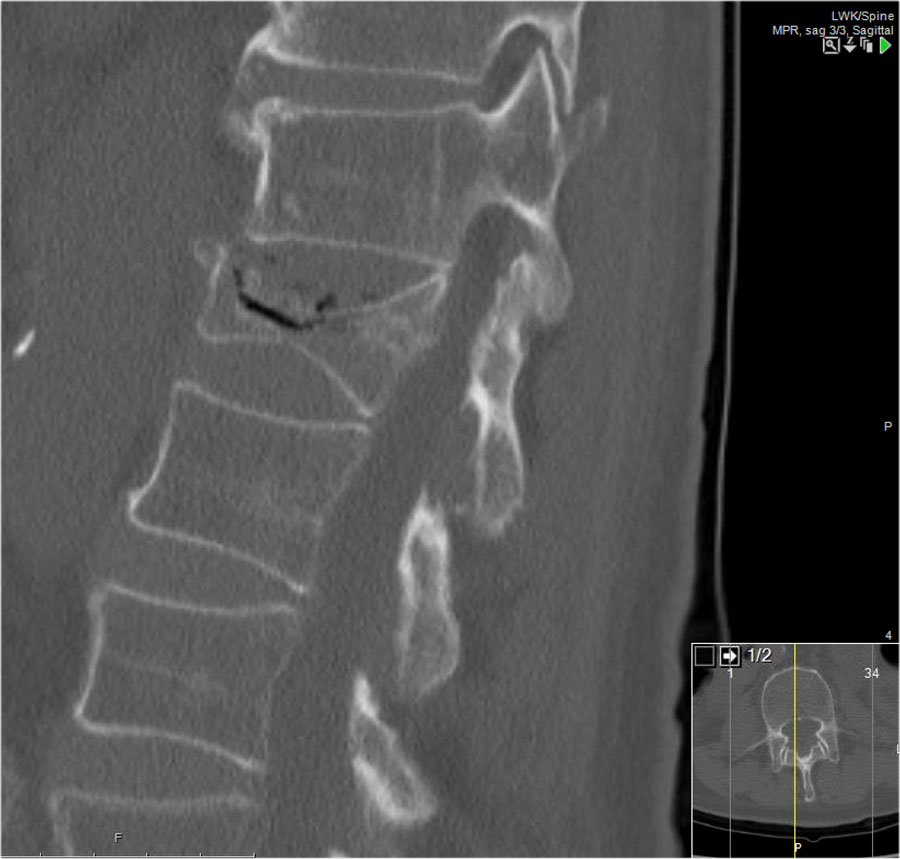

Các hình ảnh là của một bệnh nhân với hình ảnh cột sống tre điển hình do viêm cột sống dính khớp.

Sau khi ngã ngửa, không thấy gãy xương trên phim X-quang.

Tuy nhiên, CT cho thấy một đường gãy mảnh qua mặt trước thân đốt sống và cả qua mỏm gai.

Tiếp tục xem các hình ảnh MRI.